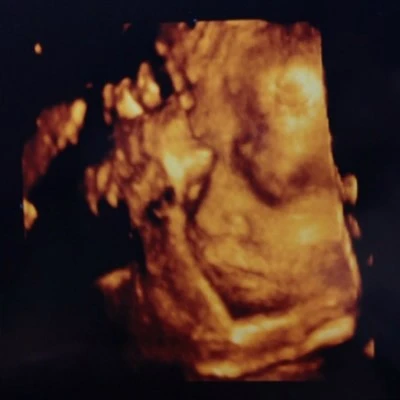

30주 + 0

콩알이가 태어났다.